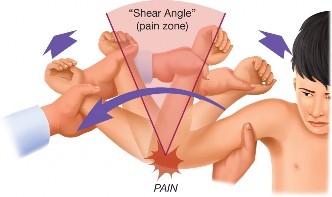

The O’Brien is one of the most common and is conducted as follows: the shoulder is flexed 90 degrees, internally rotated, and slightly adducted. Resisted shoulder flexion is performed in this position and then repeated with the shoulder externally rotated but still in 90 degrees of flexion and slightly adducted. If pain is experienced with internal rotation that is deep, anterior, and decreased with external rotation, the test is considered positive (see Fig. 2–21A–B).

Figure 2–21(A–B) O’Brien’s active compression test. Left: resisted shoulder flexion in pronation. Right: resisted shoulder flexion in supination. (From Tennent TD, Beach WR, Meyers JF. A review of the special tests associated with shoulder examination. Part II: laxity, instability, and superior labral anterior and posterior (SLAP) lesions. Am J Sports Med. 2003;31(2):301–307.)